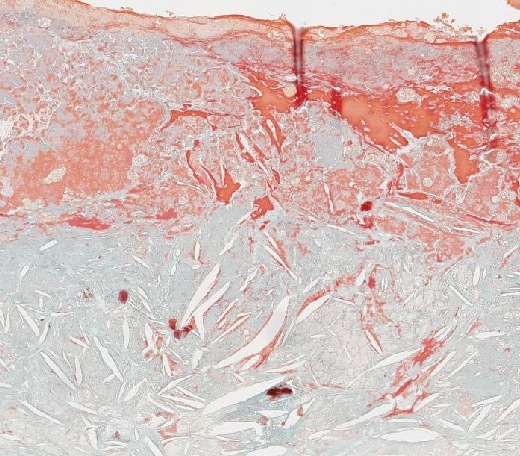

Abb. 416: Arteriosklerotische Veränderungen der Arterienwand mit Cholesterineinschlüssen und Desktruktion der Intima.